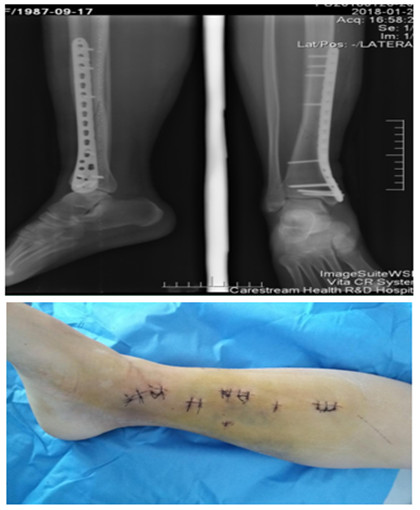

隨著時代的發(fā)展,醫(yī)療技術(shù)的不斷更新,微創(chuàng)、個性化是未來骨科的發(fā)展方向。創(chuàng)傷骨科采用MIPPO技術(shù)治療四肢骨折具有創(chuàng)傷小、術(shù)中術(shù)后出血少、傷口美觀、固定牢固、骨折愈合率高以及能夠早期功能鍛煉的優(yōu)點。延安大學(xué)咸陽醫(yī)院骨科二病區(qū)緊跟國際骨科前沿,結(jié)合國內(nèi)及地區(qū)現(xiàn)狀積極開展微創(chuàng)手術(shù),效果滿意。

我院首例脛骨骨折MIPPO技術(shù)